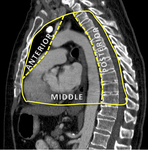

Compartimentos anatômicos do mediastino.

Do acervo de Dr. Muniappan

Veja esta imagem em contexto nas seguintes seções: